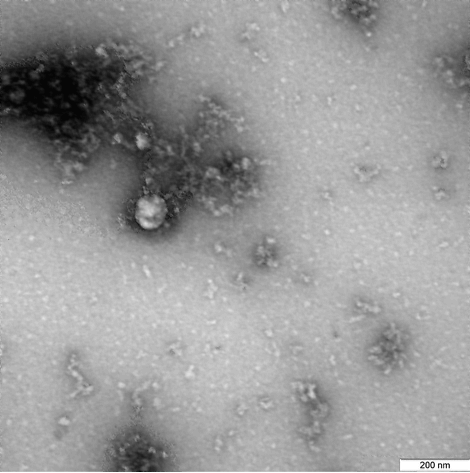

Информация Федеральной службы по надзору в сфере защиты прав потребителей и благополучия человека от 25 января 2021 г. "Учеными Роспотребнадзора получено первое изображение британского штамма нового коронавируса"

ФБУН ГНЦ "Вектор" Роспотребнадзора впервые в мире сфотографировал британский штамм коронавируса, выделенный от пациента в декабре 2020 года.

Фотография вируса под микроскопом получена в рамках продолжающегося изучения свойств данного варианта нового коронавируса, включая его структурные особенности и проявления в клеточных культурах и экспериментальных моделях с использованием лабораторных животных.

ФБУН ГНЦ "Вектор" Роспотребнадзора впервые в мире сфотографировал британский штамм коронавируса, выделенный от пациента в декабре 2020 г.